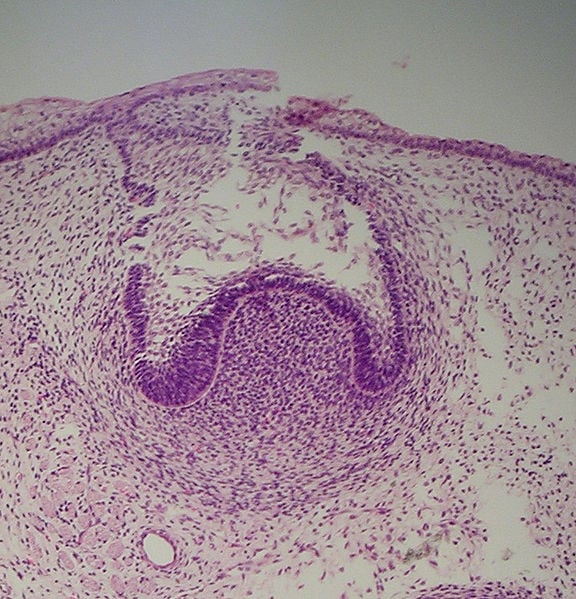

This stage is marked by the growth of the enamel organ. As the organ grows larger, it drags parts of the dental lamina along with it. The enlarging body resembles a cap sitting on the condensed ectomesenchyme, called the dental papilla. Thus, this stage of tooth development is known as the cap stage.

The enamel organ is surrounded by a fibrous capsule known as the dental follicle. It then develops into a periodontal ligament that anchors the root of the tooth to the bone. Hence, the enamel organ, dental papilla and dental follicle together serve as the tooth germ.

The center of the enamel organ forms a star-shaped layer and is therefore known as the stellate reticulum. The function of this layer is to maintain the shape of the tooth and protect the dental tissue lying beneath the layer.

As the enamel organ continues to grow, it starts resembling a bell, so this stage is known as the bell stage.

During this stage, the tooth germ is ready for the formation of hard dental tissue. The cuboidal cells at the periphery of the enamel organ form the outer enamel epithelium, whereas the glycogen-rich columnar cells border the dental papilla from the inner enamel epithelium.